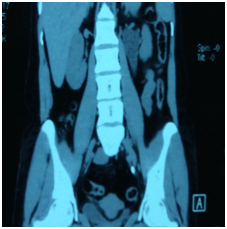

All patients who reported within 1-2 days of ureteric colic were examined, and subjected to Haemogram, KFT, Urine examination, Ultrasound and NCCT Scan (Figure 1&2) to document ureteric calculi at the time of colic with respect to location, side and size of the stone. Age and sex of the patient was noted down and SOADS regime was started for a period of 4 weeks maximum after which this MET was stopped. The routine follow up examination were performed, using the same tools to evaluate the success of the treatment after every week till 4 weeks of study period. Patients were instructed to discontinue the study medication after spontaneous stone expulsion and date of expulsion is to be recorded. For patients without stone in urinary tract on final USG/NCCT but unnoticed stone expulsion, the date of last positive stone status is to be recorded (Figure 3). For the children the dosage of the SOADS regime was half the dosage. Two - three litres of fluid which consists of Lemon juices, Oranges juices and clear water or Tea. This regime was continued for 2 weeks after which again assessment was made and if the stone did not pass then it was continued for another 2 weeks. Treatment was considered successful when stone was expelled within 4 weeks. After 4 weeks, patients who did not pass the stone were advised to undergo minimally invasive surgery depending upon the stone size and location.

Figure 3 NCCT Scan of abdomen & Pelvis showing left lower ureteric calculi.

The diagnosis of the ureteric stone was established in 3000 patients, by ultrasound and NCCT Abdomen & Pelvis. Out of 3000 pts, there were 1977 males and 1023 females with age range from 9 years to 85 years. Out of 3000 pts, 2550 pts (85%) passed stone with SOADS regime within 4 weeks. Of 2550 pts, 1657 (65%) passed stone within 2 weeks of therapy and rest 893 pts (35%) passed stone within 4 weeks of therapy (Table 3-5). 4-6 mm stone size, comprises about 1814 pts (60.46 %), while 7-9 mm comprises about 1186 pts (39.53 %). Lower the size greater the chance of the stone to pass. Stones at UVJ and lower ureter had higher incidence of passage than stones in the upper ureter. Sex had no impact on stone passage. Right sided stones (1553/1678) had increase chance of passage than left (997/1322). In patients of unilateral obstruction, there was 10 mmHg increases in both systolic/diastolic blood pressure. Uric acid stone had increased chance of passage than calcium oxalate monohydrate calculi. Fluids like Lemon, Orange and Tea consumption were associated with increased stone passage. NCCT abdomen/Pelvis was the best investigation to confirm the presence of calculi with respect to size, composition, side, location and upper tract dilatation.